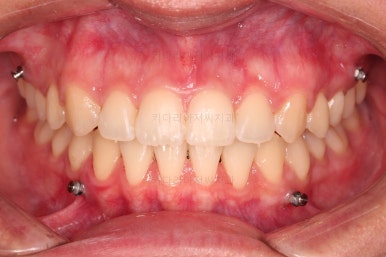

초진 시 입안의 모습입니다.

치열이 많이 삐뚠 것은 아니지만 앞니쪽이 삐뚤어 있고요. 아랫니 사이사이에 고루 틈새가 있네요.

윗니는 삐뚤고(공간부족), 아랫니는 틈새가 있다면(공간 과잉) 그 부조화는 부정교합을 의미합니다.

어금니 교합이 전반적으로 아랫니가 뒤로 빠져있는 교합이어서 맞물림이 좋지 못한 상태였어요.